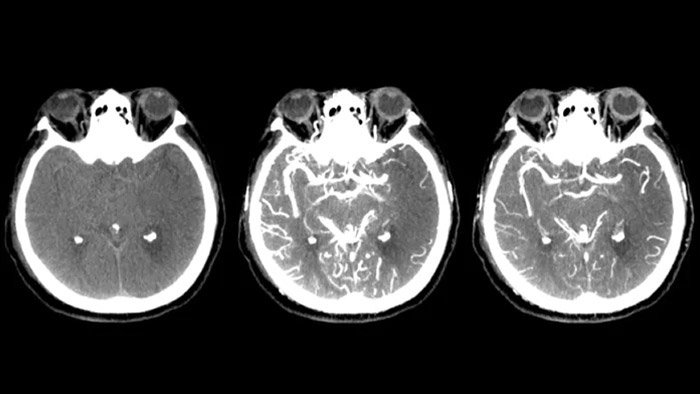

Три SmartCT

КТ-подобная визуализация

SmartCT Soft Tissue выполняет КТ-подобную визуализацию мягких тканей и дополняет диагностику инсульта тремя способами. Технология бесконтрастного сканирования помогает выявить ишемические изменения на ранних стадиях. Сканирование ранней фазы помогает определить проксимальную окклюзию. Сканирование поздней фазы с усилением контраста направлено на обнаружение коллатералей.

SmartCT Vaso IV

Провекра положения и длины тромба

SmartCT Vaso позволяет проводить визуализацию за пределами тромба с помощью перипроцедурного создания изображений дистальных сосудов при ишемическом инсульте. SmartCT Vaso — это метод сбора данных, основанный на получении КТ-изображений с помощью конического пучка и внутриартериальной инъекции контраста. Технология позволяет проводить визуализацию за пределами тромба с помощью перипроцедурного создания изображений дистальных сосудов при ишемическом инсульте. При ретроградном наполнении становится видна структура сосудов до и после тромба. 3D-схема сосудов SmartCT Vaso может использоваться при визуализации устройств для извлечения тромба.

Смотреть наполнение коллатералей

Визуализация наполнения коллатералей

Технология Dual View для одновременного просмотра ранней и поздней фаз КТ-подобной визуализации способствует определению ишемической полутени и обеспечивает визуализацию наполнения коллатералей.